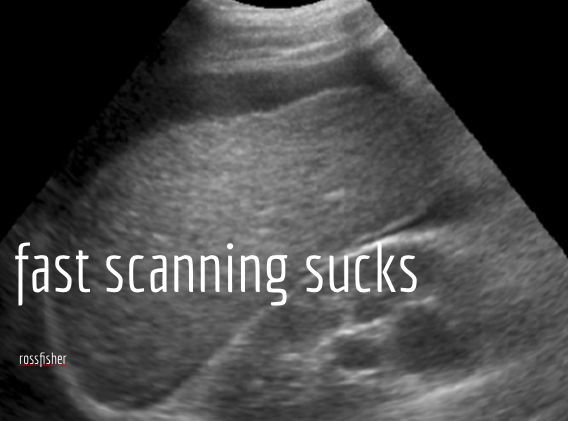

The title should arise from your preparation and gives the audience an understanding of the direction and nature of your talk, even highlighting the tenor of your delivery. “FAST sucks” is likely to be a different presentation than “FAST- is a coin toss better?” and similarly “FAST- making decisions on 50% accuracy.” An interesting title stimulates…interest. A challenge or a question engages the audience before you begin, makes them think and bring an opinion to the front of their mind. This is useful if the presentation intends to challenge that opinion rather than simply presenting a pile of data and allowing the audience to decide at the end. Your title is an essential part of a good presentation. Use it for the best possible start.